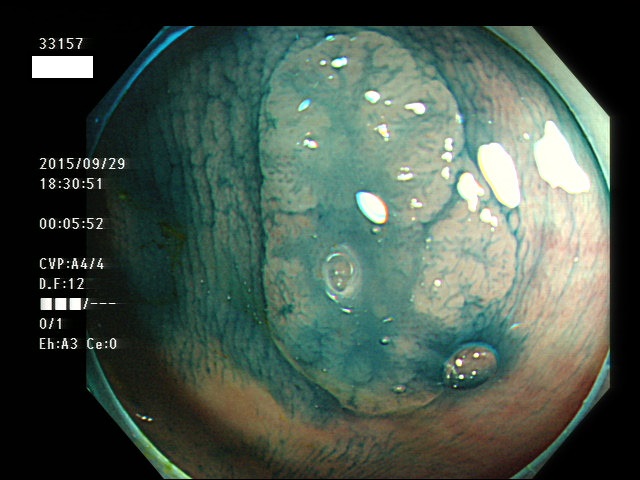

上記100名より抽出した平坦・陥凹型腺腫(=癌化の危険が高いが見落としやすい病変)の内視鏡写真